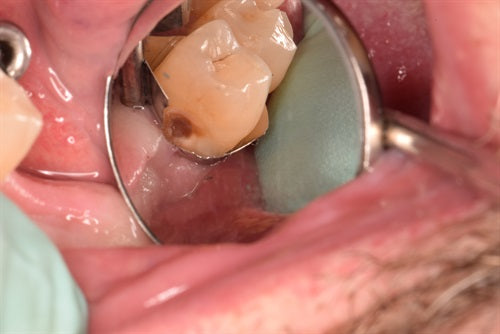

A method to restore root caries

Introduction: Great case submitted by Dr. Ahmad Fayd. I get these root caries frequently, where the occlusal surface is usually intact with a huge defect on the root. In my... Read More